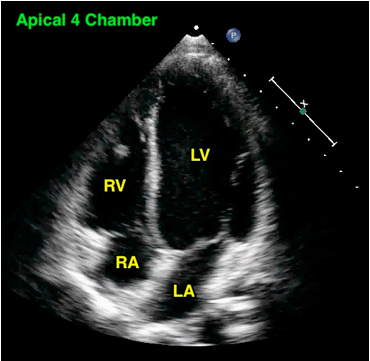

what are the different planes of MRI scans

short axis (parasternal)

long axis (parasternal)

4 chamber ( LA LV RA RV )

2 chamber ( LA LV )

3 chamber ( LV LA A )

label these